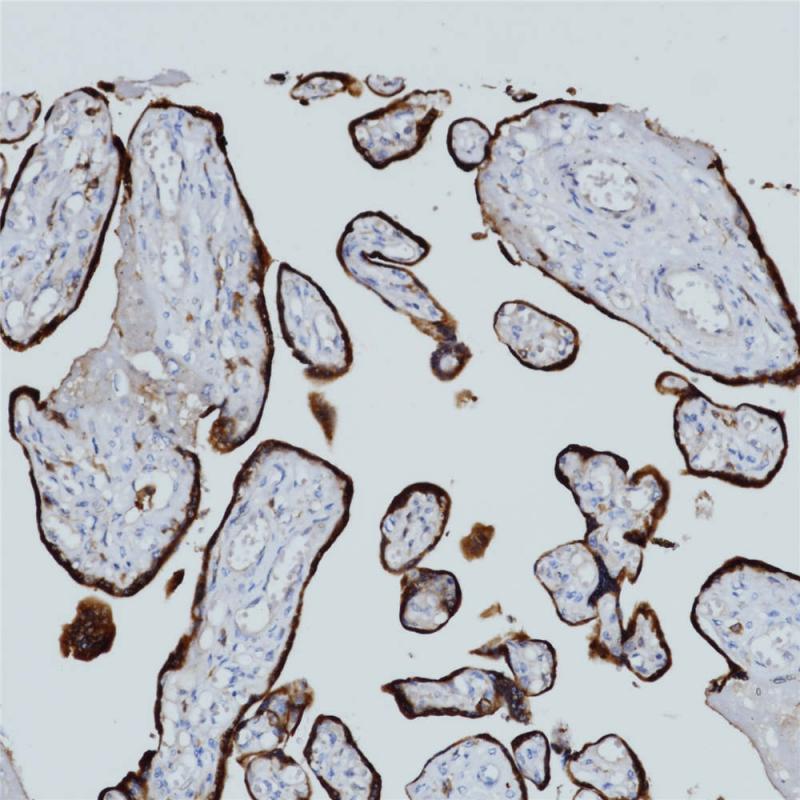

p40 重组兔单克隆抗体

p40是p63蛋白的亚型之一,通常表达于复层上皮组织的基底细胞层或祖细胞层(如鳞状上皮、尿路上皮、支气管上皮)、某些腺上皮的基底细胞(如前列腺)、乳腺和唾液腺的肌上皮细胞、滋养层及胸腺上皮细胞。肿瘤组织中,p40在鳞状细胞癌中具有特异性表达,但肺腺癌中罕见表达,其对于肺鳞癌的敏感性类似于p63,但专一性明显优于p63,可用于肺鳞癌和肺腺癌的鉴别诊断。

阳性对照

前列腺

亚细胞定位

细胞核